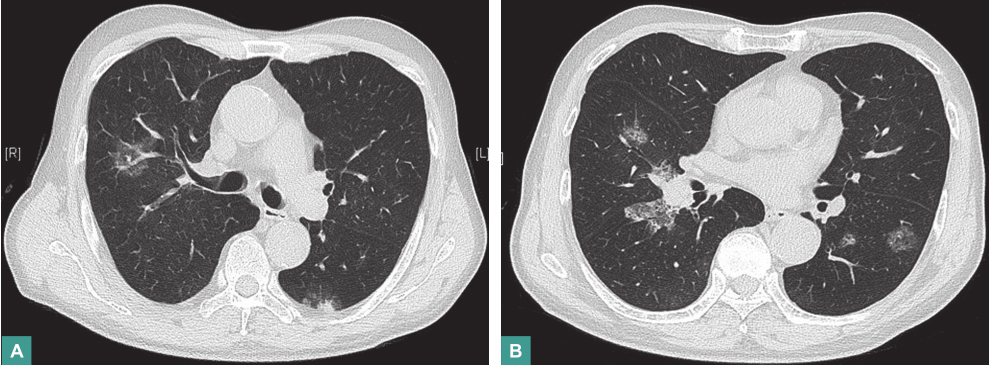

口服泼尼松23天后,患者咯血症状无改善,自行停药。停药1个月后复查胸部CT,提示双肺病灶较前增多、增浓(图2)。转胸外科行胸腔镜下肺活检,病理结果示:病灶边缘腺泡腔内肿瘤组织呈充填式生长,病灶中央见不规则互相吻合、沟通血管腔隙,内皮被覆异型内皮细胞(图3)。术后病理诊断:肺血管肉瘤。由于患者发病后多次查体,未见皮肤、乳腺异常,无骨骼疼痛,心脏彩超、全腹彩超皆未发现血管性肿瘤征象,故判断肺部病灶为原发。

图2 停药1个月后胸部CT表现

本例患者以咯血为主要表现,胸部CT提示双肺多发混合密度病灶,病灶中可见致密影,边缘见晕轮征,经外科胸腔镜下肺活检病理确诊为血管肉瘤,再结合患者无异常阳性体征,腹部及心脏彩超未见肺外原发灶,故可诊断原发性肺血管肉瘤。因此,对于病因不明的咯血、气促、双肺多发磨玻璃影伴中间致密影类似晕征病灶的病例,应考虑原发性肺血管肉瘤可能。尽早行组织病理检查有助于早期诊断及治疗,以改善预后。